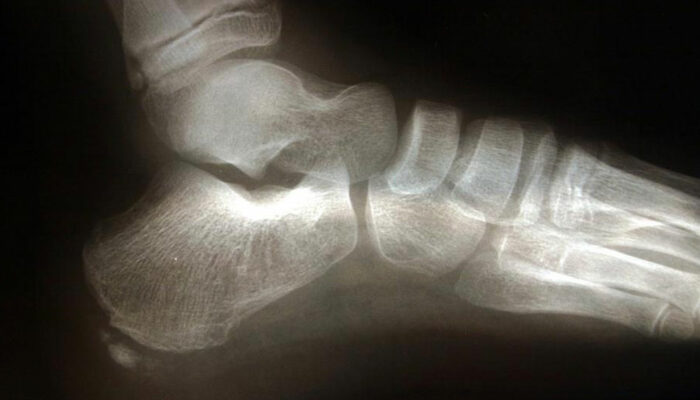

Commonly affecting athletes who frequent activities include running and jumping, heel spur is caused due to calcium deposits on the underside of the heel bone. The symptoms include inflammation of tissues and tendons near the spur, pain while walking or jogging, formation of calluses, swelling or redness of the affected part of the heel. The pain that is experienced is often sharp and stabbing. Sometimes that pain can go away to be replaced by a dull throbbing that aggravates while doing activities such as walking, jumping, jogging, or running.